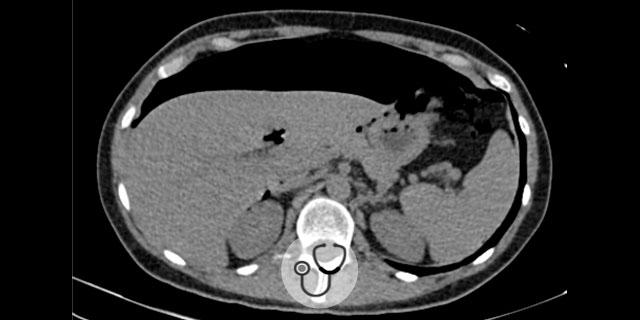

Paciente 50 anos, sexo feminino, dá entrada na emergência relatando dor abdominal no quadrante superior e inferior esquerdo.